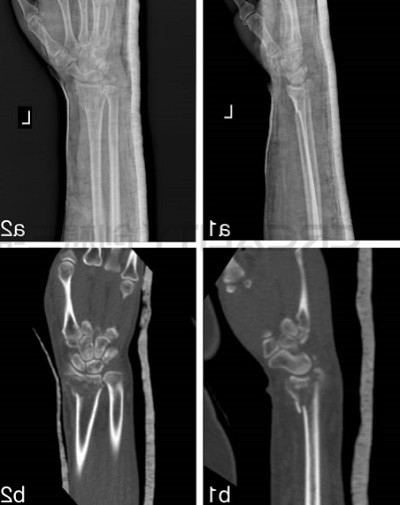

从以前跟踪过的案例中,其中3D打印机已被用于创建假肢制造手臂模型以帮助修补骨折,甚至制作植入物来治愈损伤,但在本次研究中,研究人员评估了该技术在其中进行改进的能力。48名患有桡骨远端骨折的患者(最常见的上身损伤类型之一)参与了这项研究。

CT数据以DICOM格式存储,然后在3D打印机中使用PLA耗材打印之前通过Mimics软件进行转换。科学家们报告了3D打印模型的成功,因为它们清楚地显示了骨折的位置,这种手术每次大约需要两个半小时。

“在3D模型上,我们根据骨折线分割骨折碎片,然后用K线暂时复位碎片,然后用金属板和螺钉固定碎片,”研究小组说:“通过这种方式,所需植入物的类型和尺寸在术前确定,我们可以选择合适的金属板和螺钉。”